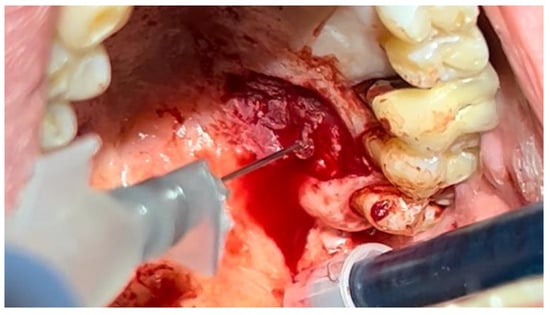

The patient was prepared for the surgical procedure with antibiotic therapy (Amoxicillin + Clavulanic Acid 875/125 mg) and 2% Chlorhexidine rinses starting the day before the surgery. Following the guidelines for patients with hypertension (Figure 1), the excision was performed with the complete removal of the lesion, adhering to standard surgical procedure techniques (Figure 3). Post-excision, hemostasis was achieved using Glubran II surgical glue. In this case, an endodontic needle was used for material application, allowing single droplets to be applied directly to the surgical site (Figure 4). Hemostasis was rapidly achieved in the areas where the glue was applied. The material was carefully deposited around the perimeter of the surgical site, ensuring individual droplets were placed without excessive application (Figure 5).

Figure 4. Hemostasis control at the surgical site following excision of the lesion with Glubran II using an endodontic needle.